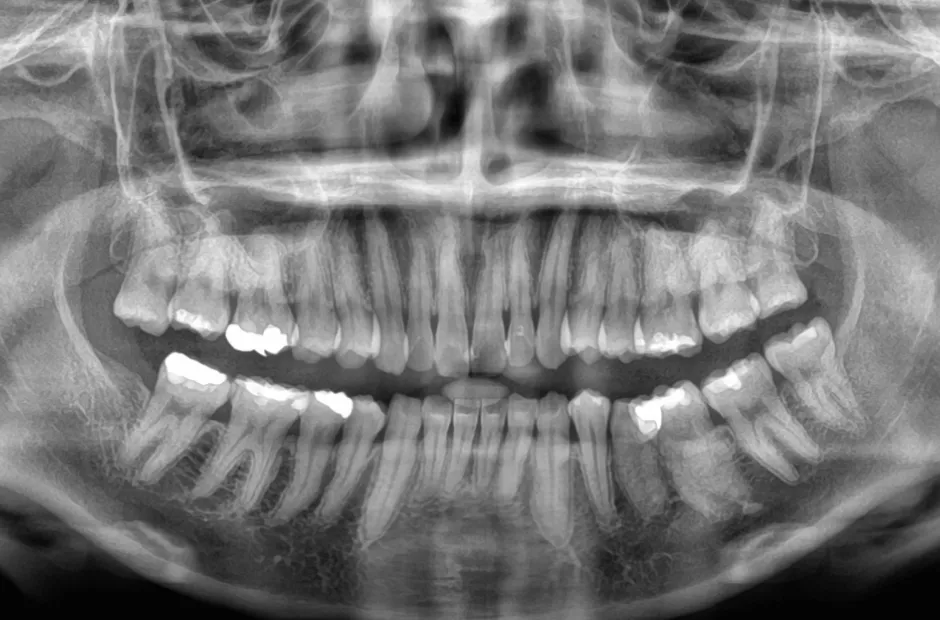

叢生

| 診断名・主訴 | 叢生 |

|---|---|

| 年齢・性別 | 43歳・女性 |

| 治療期間・回数 | 2年7か月 27回 |

| 治療に用いた主な装置 | 舌側矯正 |

| 抜歯部位 | 両顎4,4 |

| 治療費 | 100万円(税抜) |

| リスク・副作用 | 装置による違和感・疼痛・歯肉退縮・歯根吸収・虫歯のリスクなど |